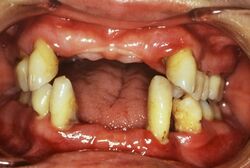

「歯周病患者は年齢とともに多くなります。しかし、治療を通じた私の実感ではもっと若いうちからかかる人も多く、成人の8割は該当するのではないかとみています。『サイレント・ディシーズ』(静かに進行する病気)と呼ばれ、気づいたときはすでに遅く40代で総入れ歯という患者さんが実際に存在するからです」

歯のぐらつきや歯ぐきからの出血、歯肉がぶよぶよしているなどの症状がサイン。歯が長く見える場合も要注意だ。